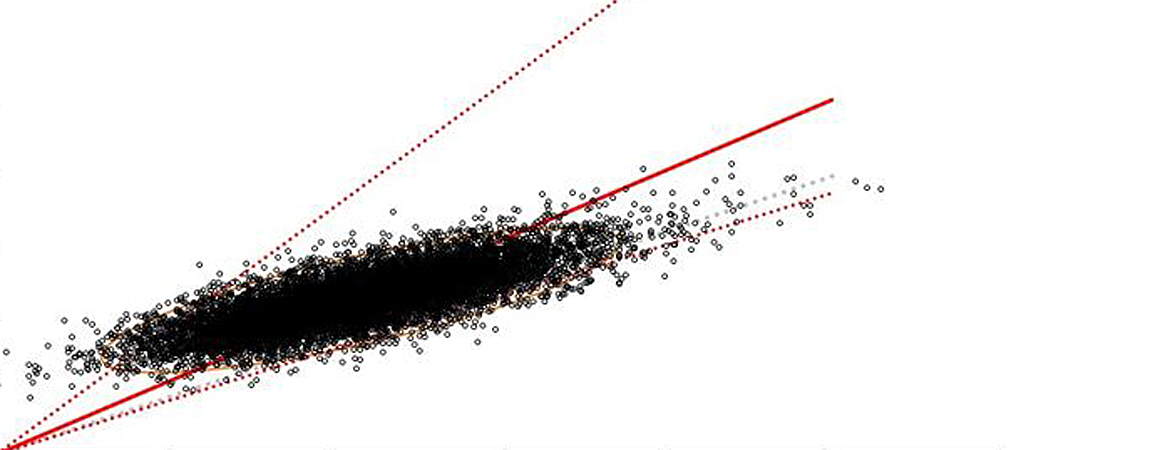

Axel Rüfer, Christine Bapst, Rudolf Benz, Jens Bremerich, Nathan Cantoni, Laura Infanti, Kaveh Samii, Mathias Schmid, Jean-Paul Vallée (Author) Role of liver magnetic resonance imaging in hyperferritinaemia and the diagnosis of iron overload Fulltext PDF Fulltext HTML